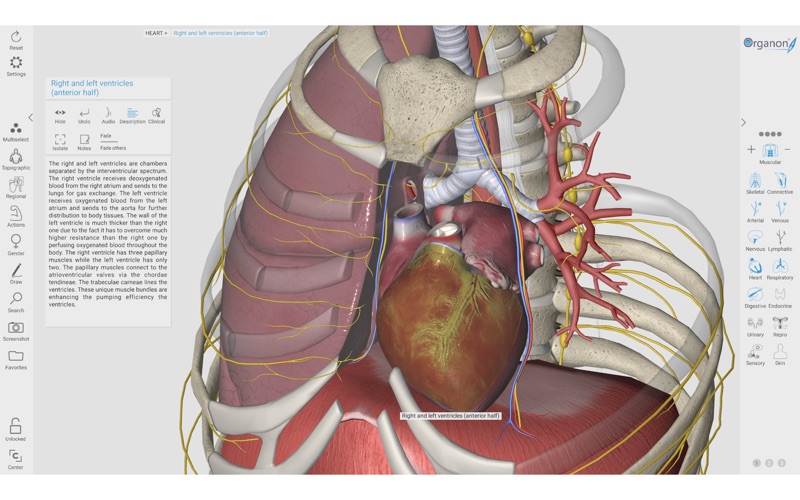

2. 3D Organon Anatomy is an interactive anatomical atlas featuring all 15 human body systems.

5. All anatomical definitions and clinical correlations are written by professors of anatomy and medical professionals.

6. It features all body systems: Skeletal, Connective, Muscular, Arterial, Venous, Nervous, Lymphatic, Heart, Respiratory, Digestive, Endocrine, Urinary, Reproductive, Sensory organs, and Integumentary (skin).

10. 3D Organon unfolds life-like high resolution 3D models covering every aspect of the human body.